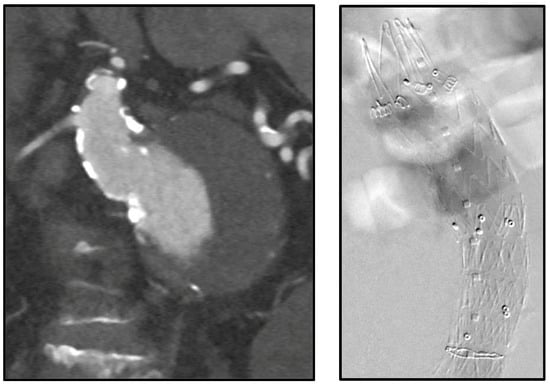

Physicians in our institution have utilized endoanchors prophylactically for hostile necks (Figure 4) and in those necessitating revisions for proximal neck dilation (Figure 5) or concern for type Ia endoleaks.

Figure 5. Intraoperative images of previous endograft with hostile neck anatomy (proximal neck had dilated to the same size as existing endograft) treated with eight endoanchors.